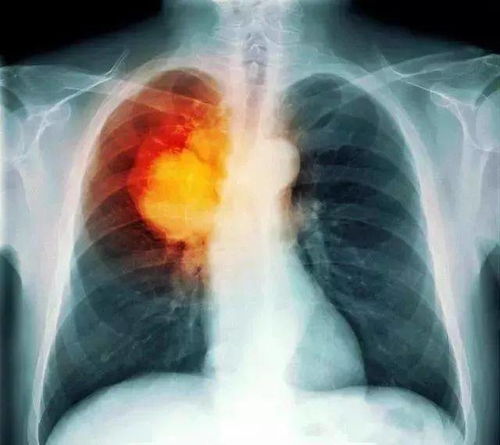

三、警惕可能的恶性情况

虽然左肾偏强回声多数情况下是良性的,但也存在少数恶性情况,如肾细胞癌。这类恶性肾脏肿瘤在超声下可能表现为强回声,并伴随血流丰富、占位效应等特征。其他罕见的恶性肿瘤,如高级别尿路上皮癌,需要结合病理活检进行确诊。